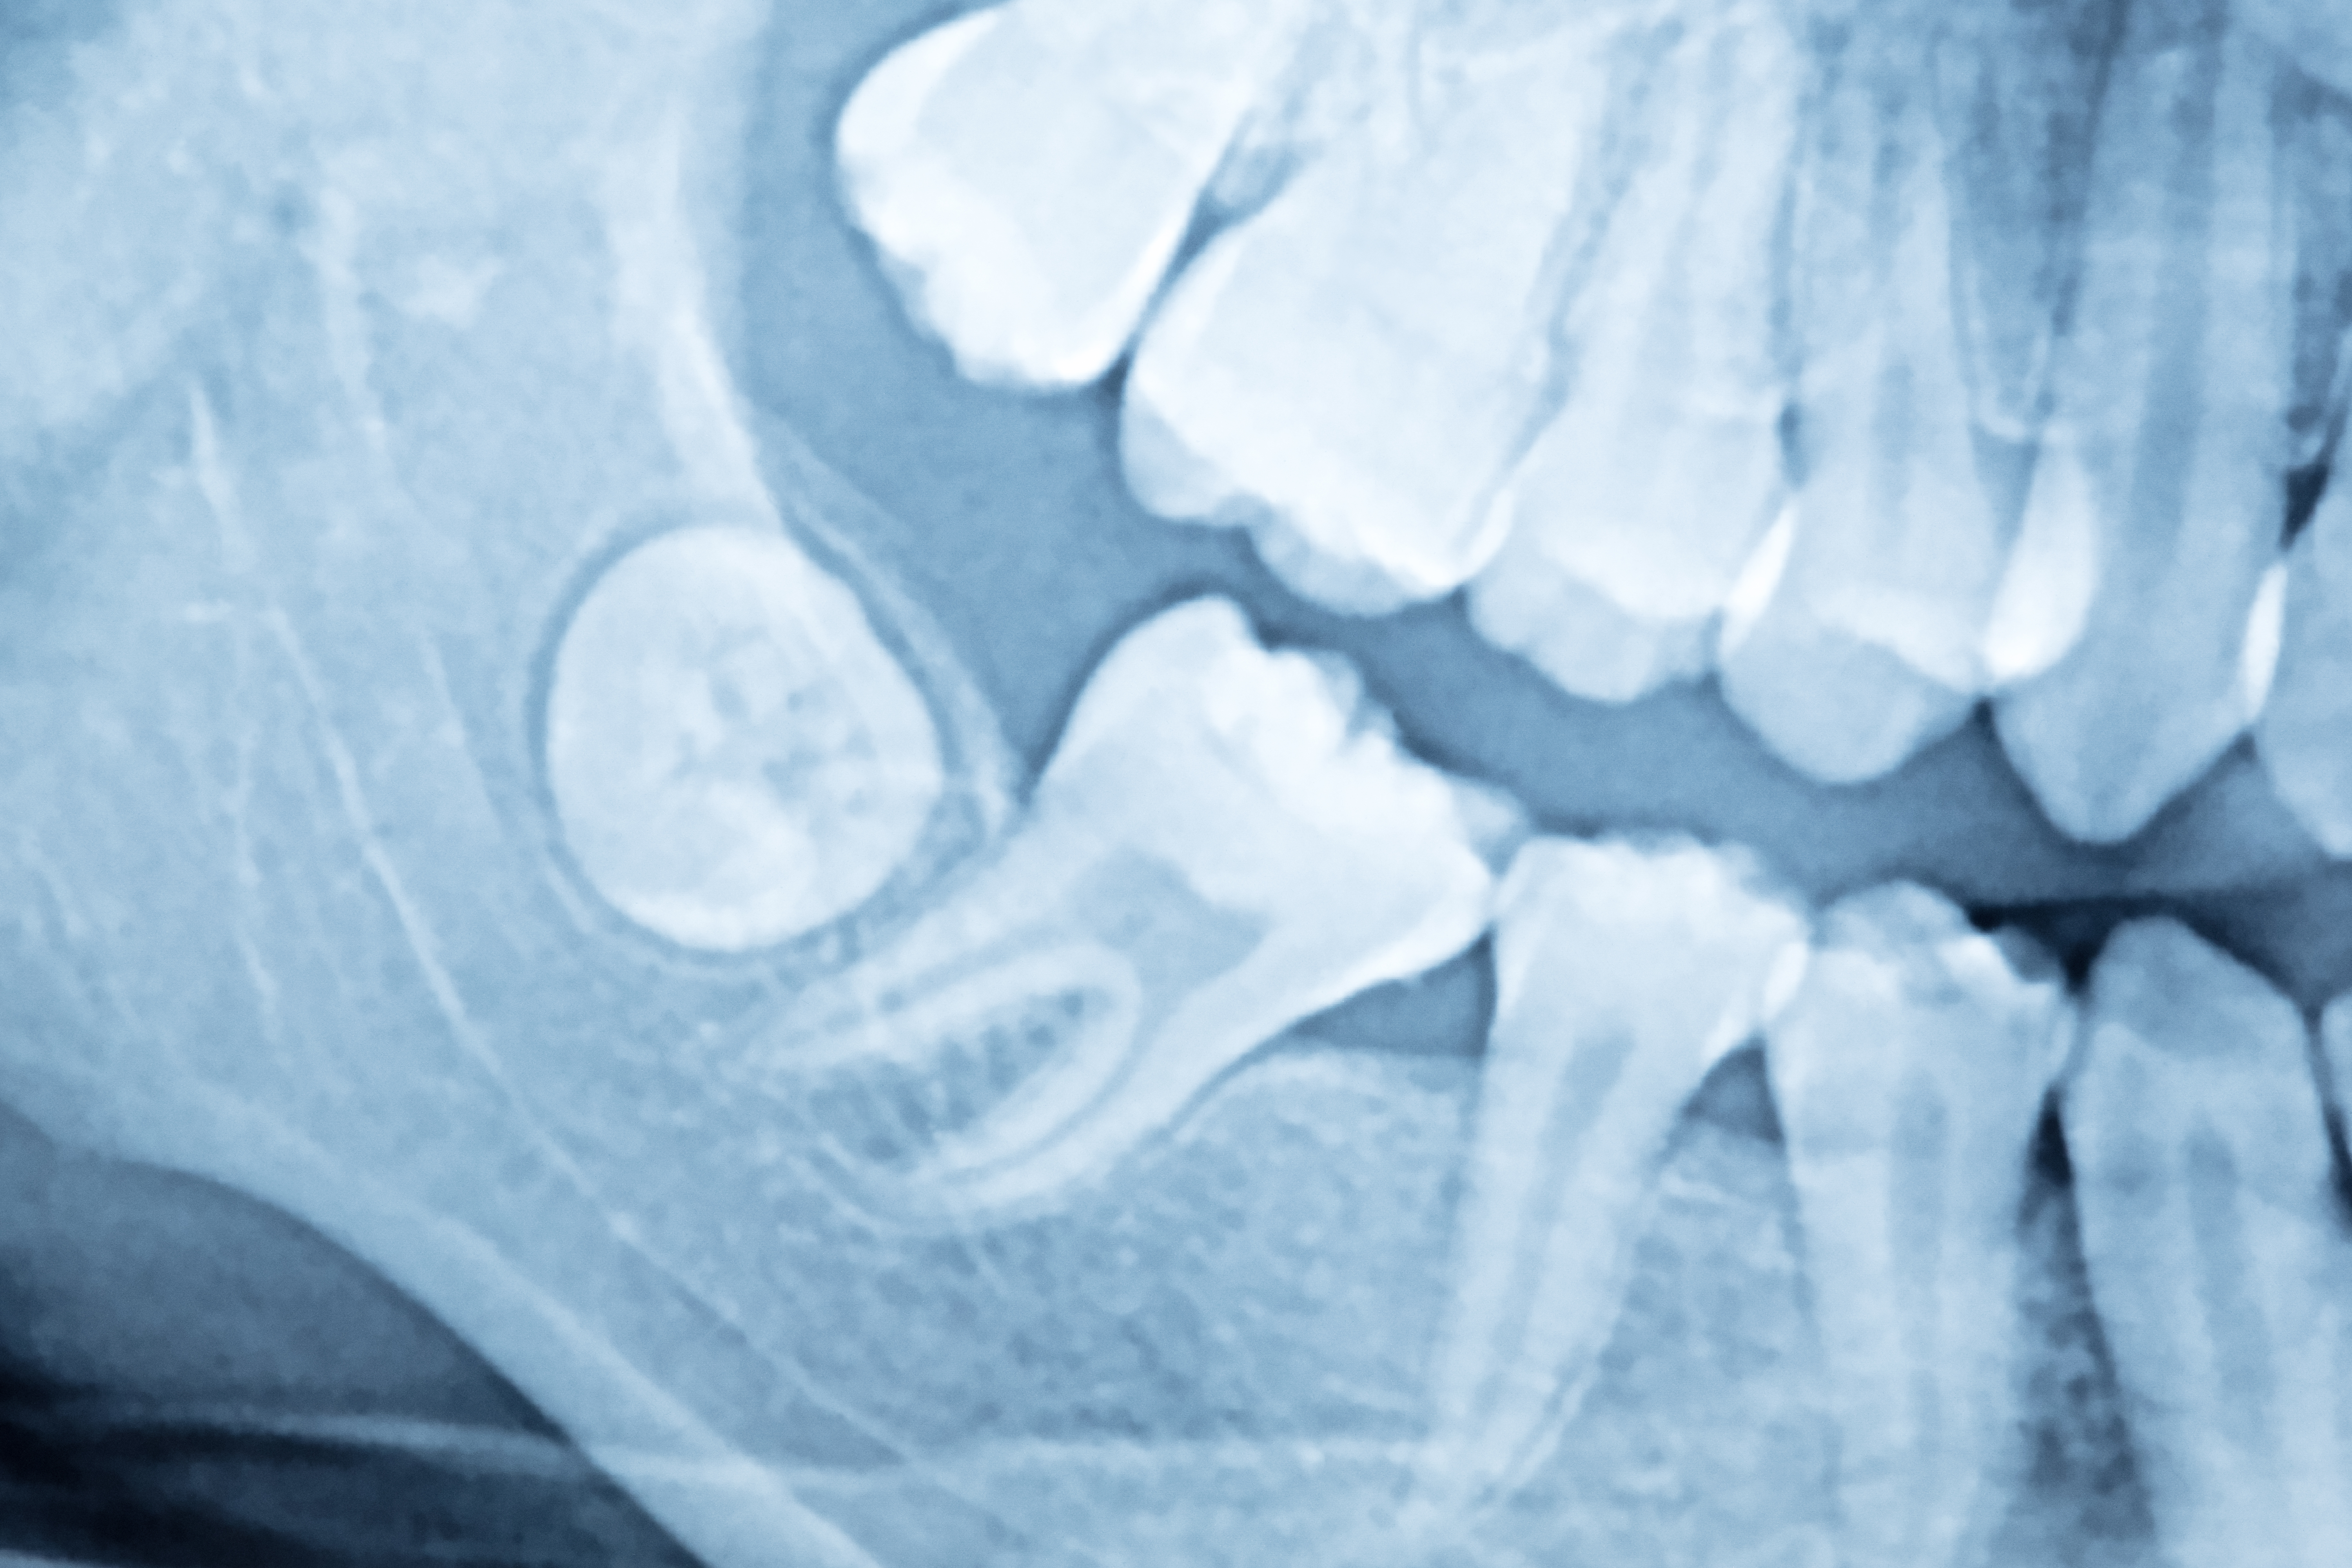

Если зуб мудрости так и не прорезался к положенным годам, его называют ретинированным (то есть полностью закрытым десной). Необходимость удаления может быть связана с давлением его коронковой или корневой части на соседние зубы. Также в качестве вероятных осложнений возможны боли в ухе и при глотании, увеличение лимфоузлов из-за давления на ткани и нервные окончания.

Дистопированным- называют зуб, который вырос (полностью или частично) под наклоном от своего естественного расположения, вплоть до лежания горизонтально. Такой зуб часто вызывает нарушение прикуса и травмирует мягкие ткани рта.

Для качественного извлечения ретинированного или дистопированного зуба от врача требуется высокая квалификация и многолетний опыт. По сути, речь идёт о малом хирургическом вмешательстве. Чтобы всё прошло успешно, предварительно назначается обследование (рентгенография или компьютерная томография), которое позволяет оценить расположение зуба и разветвлённость его корней, а также выбрать подходящую тактику удаления.